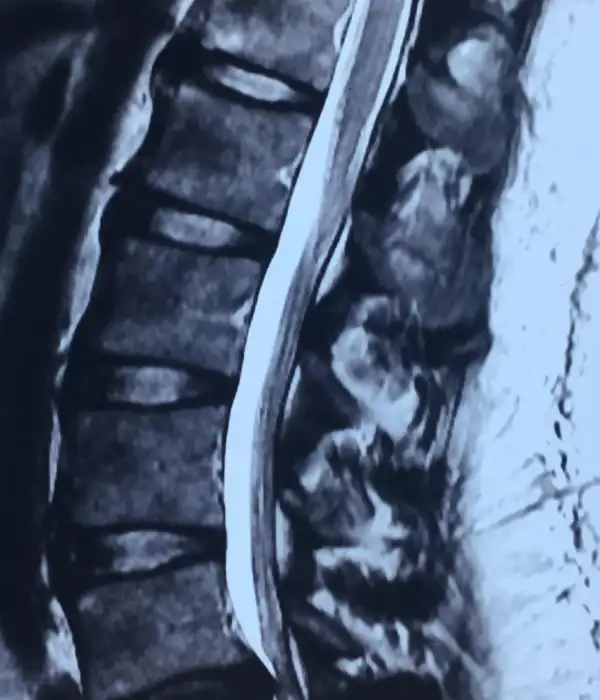

Degenerative Thoracolumbar Spine Disorders

Degenerative thoracolumbar disorders are becoming increasingly prevalent as patients have longer, healthier, and more active lives. While much of the treatment is nonsurgical, there are certain conditions that require surgery. Some degenerative diseases can be easily treated with small, minimally invasive procedures, but others require large, reconstructive operations. The spine surgeons at Kauvery Advanced Spine Centre have considerable experience treating the entire spectrum of degenerative disorders, as well as in-depth knowledge of the success rates of each procedure. Mini open and minimally invasive transthoracic disc surgery is performed here.

Thoracolumbar conditions treated include

- Disc herniations

- Disc Stenosis

- Degenerative Adult Scoliosis

- Kyphosis

- Facet joint arthropathy

- Disc SI joint degeneration